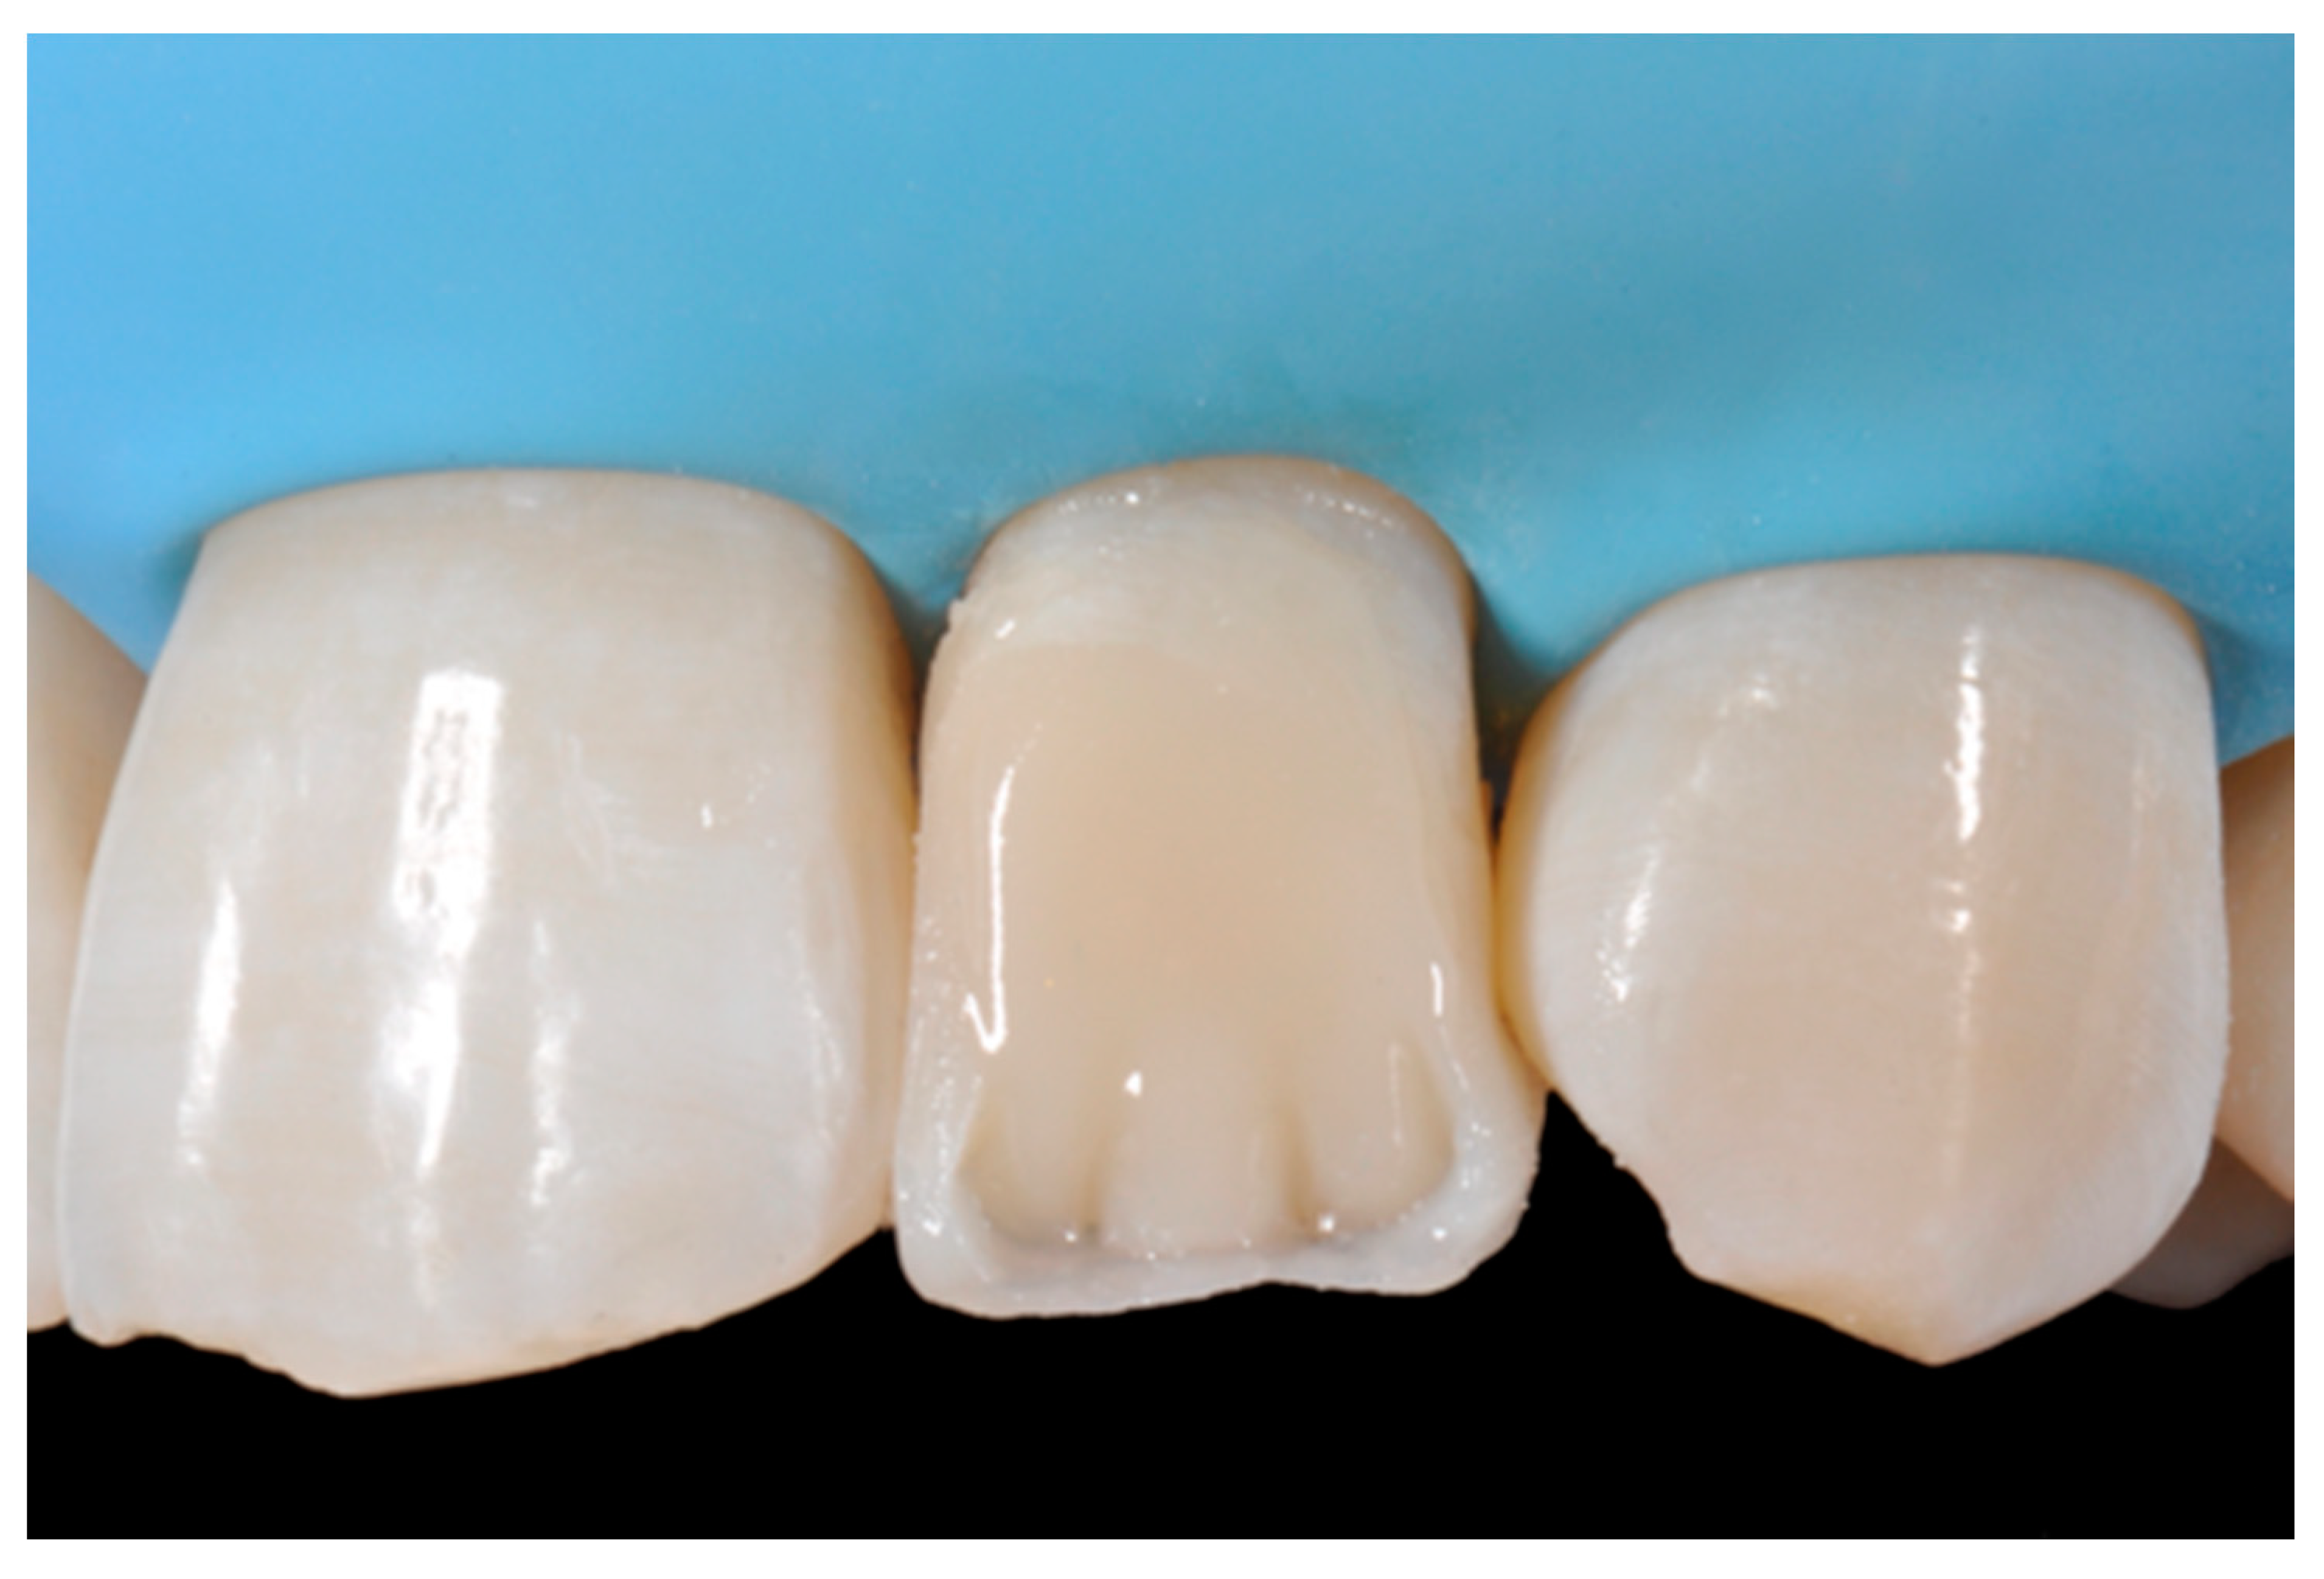

Figure 12.

Enamel layer applied. Reprinted from Restauri diretti nei settori anteriori, G. Paolone, S. Scolavino, © 2021, with permission from Quintessence Publishing Italy.